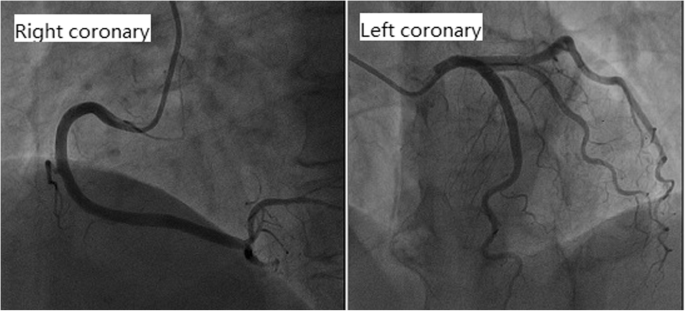

Cardiac examination at admission showed elevated repeated brain natriuretic peptide precursor (Pro-BNP), C-reactive peptide (CRP), high sensitivity C-reactive peptide (hs-CRP) and troponin T (cTnT) levels (Table 2). ECG revealed T-wave inversion on the inferior and anterior walls and an extended QT interval (QT/QTc 780/762 ms) (Fig. 3 a). Emergency bedside TTE showed left ventricular ballooning, apical dyskinesia, and abnormal diastolic function (LVEF being 36% by Simpson’s method) (Fig. 4 a b c), which was considered Takotsubo cardiomyopathy. Coronary angiography (CAG) performed 2 days later found no significant coronary arterial stenosis (Fig. 5), but left ventricular angiogram demonstrated the typical apical LV wall motion abnormalities and a peculiarly shaped LV (a round bottom and narrow neck), resembling the type of bottle used in Japan for trapping octopus (Figs. 6). Therefore, the patient was diagnosed with Takotsubo cardiomyopathy and treated with angiotensin converting enzyme inhibitor (ACEI), β-blocker and L-carnitine.

The patient’s CAG showed no obvious abnormality, but the left ventricular angiogram revealed typical apical ballooning and wall motion abnormalities. TTE at admission showed LV apical ballooning, abnormal systolic function, and LVEF of 36% by Simpson’s method. In addition, the 70-year-old patient had elevated Pro-BNP, inverted T-wave and extended QT interval, all of which met the diagnostic criteria of TTC. Thus, we concluded that TTC was induced by pituitary crisis. After 10 days of treatment, the level of Pro-BNP was reduced, and T-wave inversion and QT interval extension disappeared in the ECG. In particular, there were no LV apical ballooning or left ventricular wall motion abnormalities, which suggested the recovery of the affected myocardium and explicit TTC diagnosis.